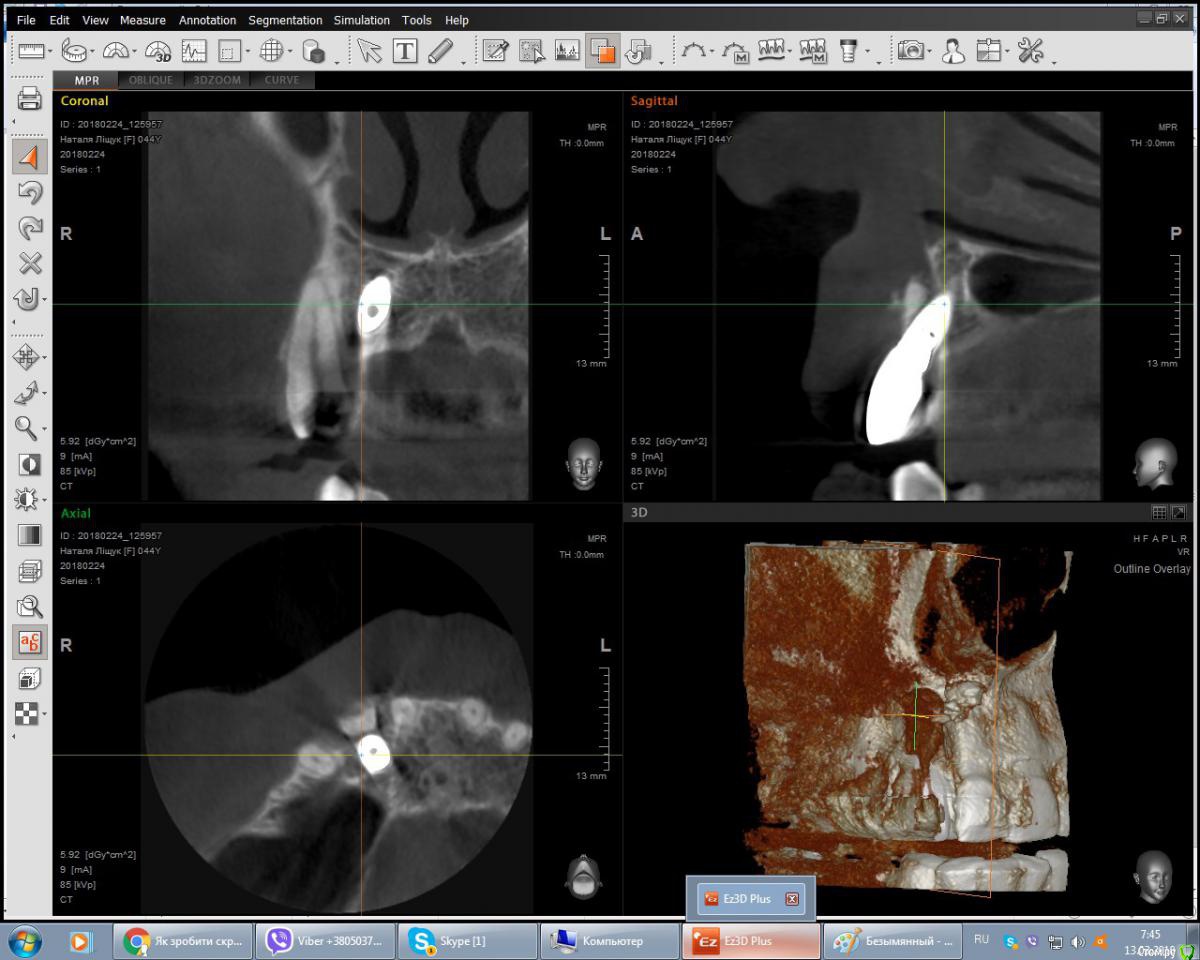

дашутка Опубликовано 13 марта, 2018 Автор Поделиться Опубликовано 13 марта, 2018 (изменено) Прикрепляю скрин КТ Изменено 13 марта, 2018 пользователем дашутка Ссылка на комментарий

дашутка Опубликовано 13 марта, 2018 Автор Поделиться Опубликовано 13 марта, 2018 Кт делала за неделю до удаления, после удаления снимок не делали. Фотку, попробую завтра сделать днём, чтобы качество было получше. Ссылка на комментарий